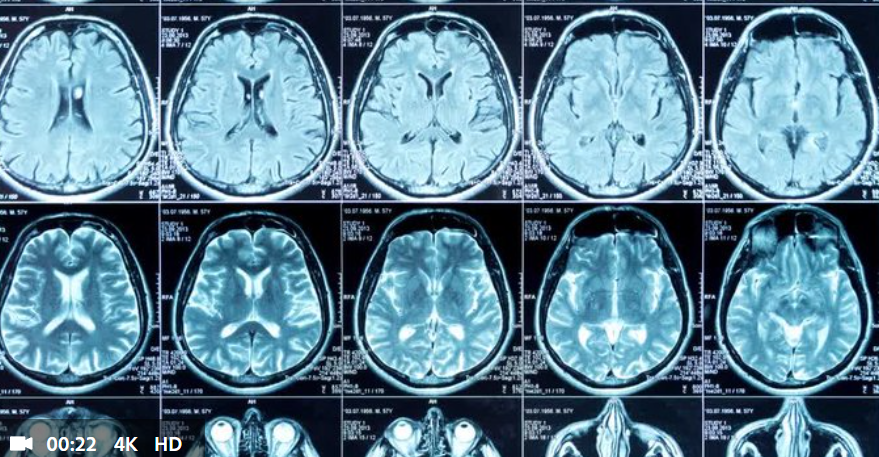

Magnetic Resonance Imaging (MRI) is a common and valuable medical imaging technique used to diagnose a wide range of health conditions. Many patients wonder if MRI scans could increase their risk of developing cancer. Here’s what you need to know.